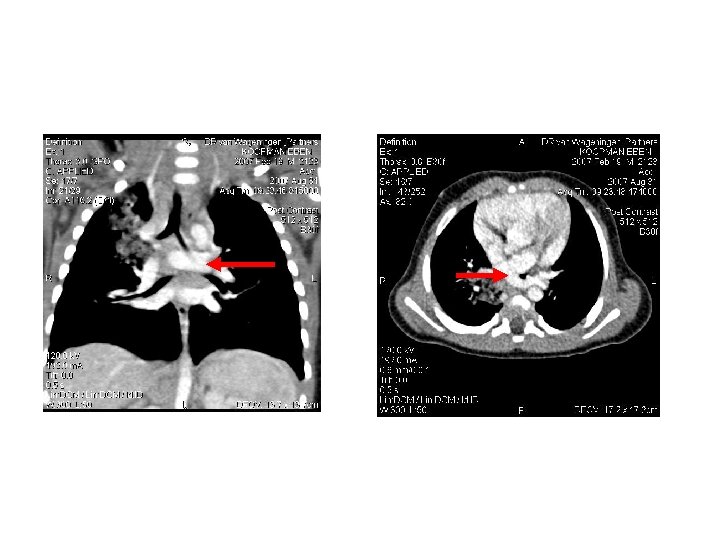

Chest X-ray in severe asthma • Relevant in search for underlining complications – Pneumonia – Air leakages – Collapse • Ventilated patients

Asthma complications • • • • Pneumothorax Pneumomediastinum Pneumopericardium Pulmonary interstitial emphysema Pneumoretroperitoneum Cardiac arrhythmias Myocardial ischaemia or infarction Mucus plugging Atelectasis Pneumonia Electrolyte disturbances – Hypokalaemia – Hypomagnesaemia – hypophosphataemia) Lactic acidosis Hyperglycaemia Theophylline toxicity

Bronchoscopy and BAL • Mucous plugging may be a reason why a small number of children does not improve despite maximal therapy • Asthmatic children with massive bronchial cast or plastic bronchitis have been described • Children being ventilated and whose condition is deteriorating despite maximal therapy , severe mucous plugging must be considered • Bronchoscopy in this setting may be very dangerous